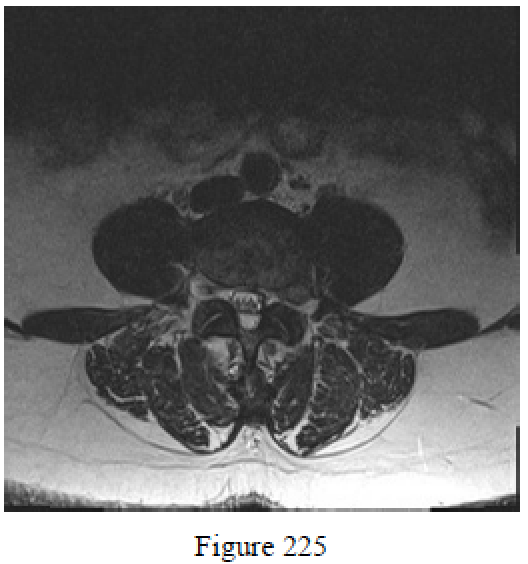

Question 225

Figure 225 is an axial MR image at L4-5 of a 57-year-old woman who has had 3 months of back pain that radiates into her left anterolateral thigh, anterior shin, and medial ankle. Her pain has persisted after participating in physical therapy and receiving medications and an epidural injection. She has a positive straight-leg raise result and weakness in the anterior tibialis (4/5). What is the most appropriate treatment?